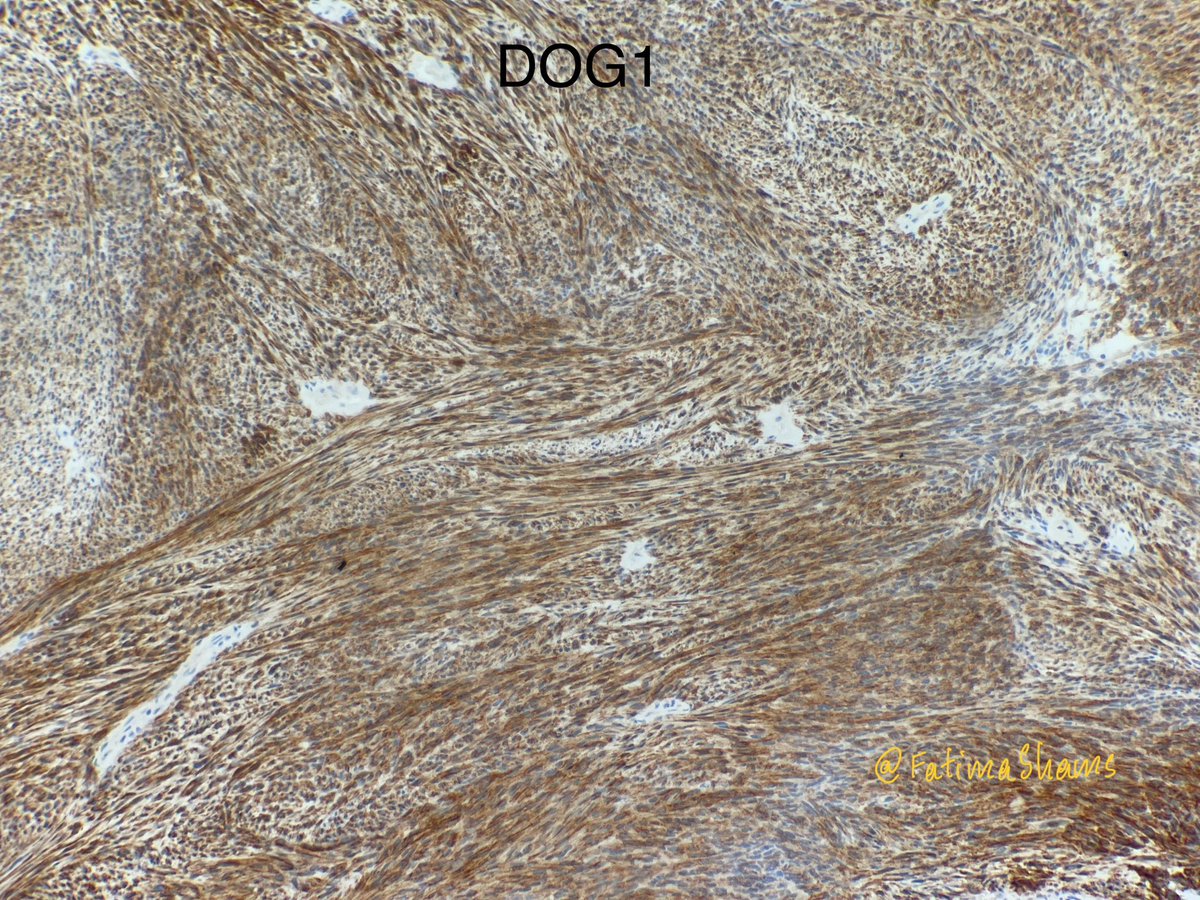

@FatimaShamsPath

@annsmiley78 Set 4 (final):- Detailed history revealed a radiological history (in 2022) of “large anorectal soft tissue mass” Following this the two most important IHCs to confirm the diagnosis was performed. Diagnosis? Learning point: - Never underestimate the importance of detailed